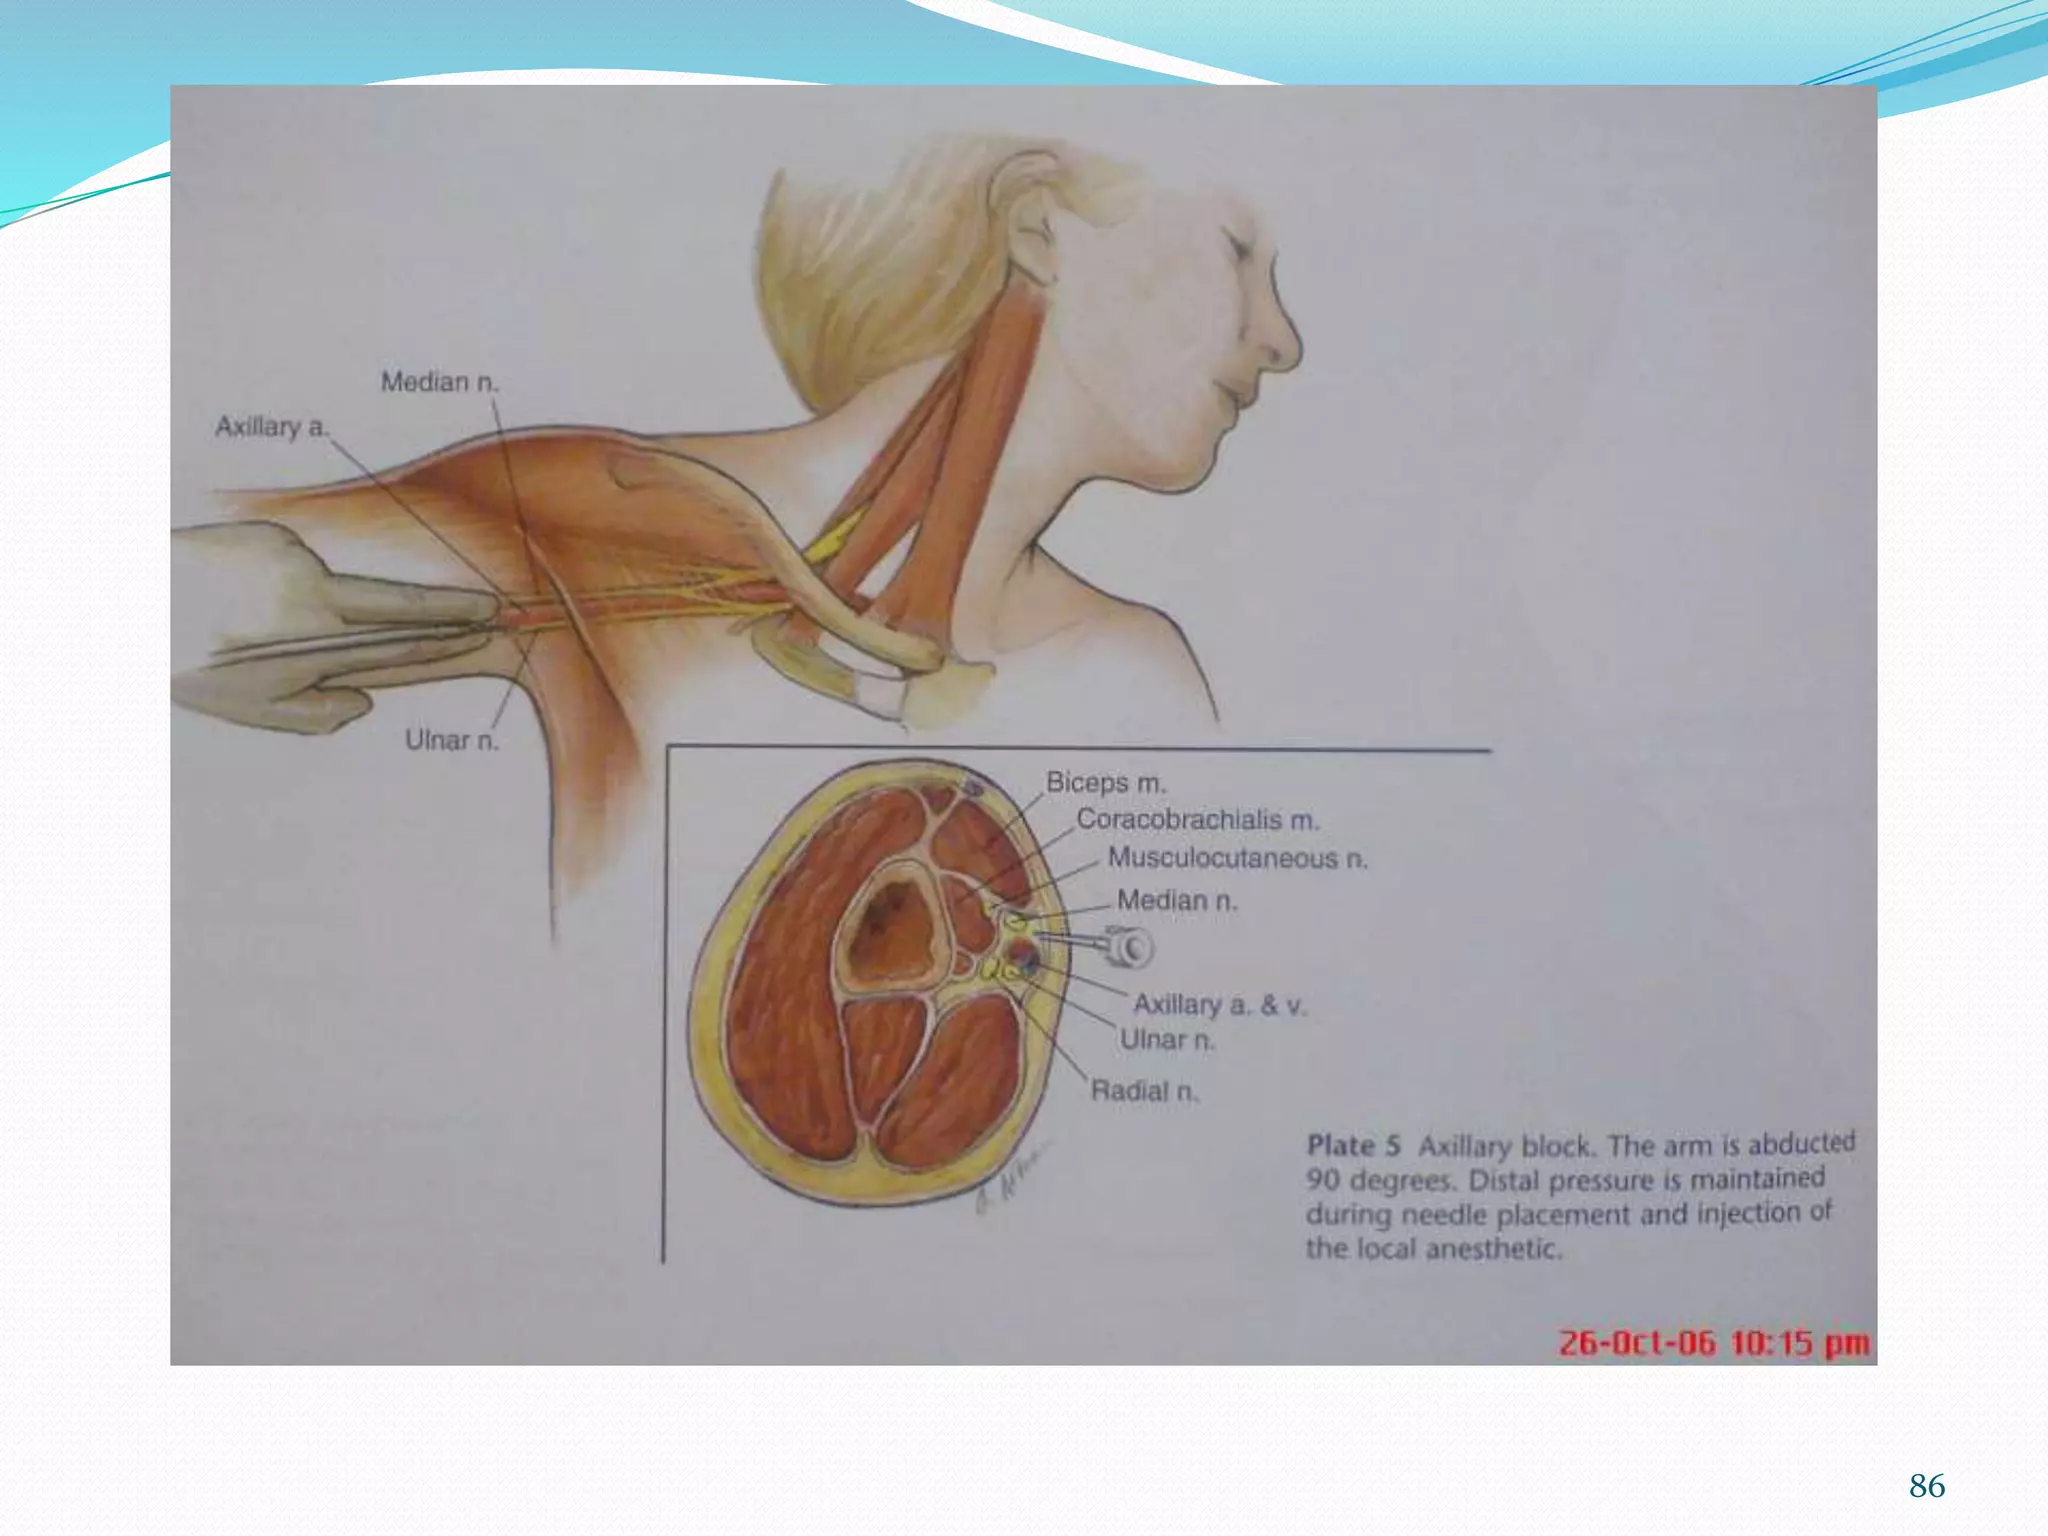

This document provides an overview of brachial plexus anatomy and techniques for brachial plexus nerve blocks. It begins with a description of the brachial plexus formation from cervical and thoracic nerve roots and its branching pattern. Four main approaches for brachial plexus nerve blocks are described: interscalene, supraclavicular, infraclavicular, and axillary. Details are provided on the anatomy and techniques for performing interscalene and supraclavicular brachial plexus blocks. Ultrasound guidance is discussed as an advancement which allows real-time visualization of needle and nerve. Complications are also summarized.